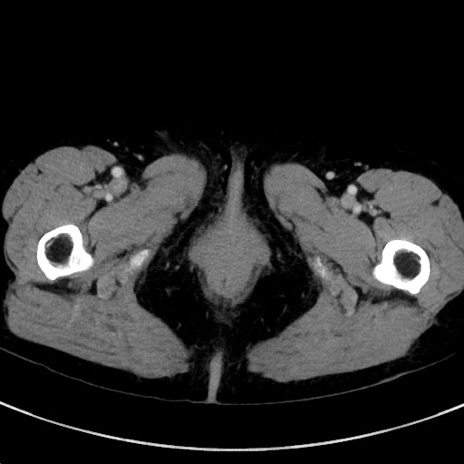

冠状断像